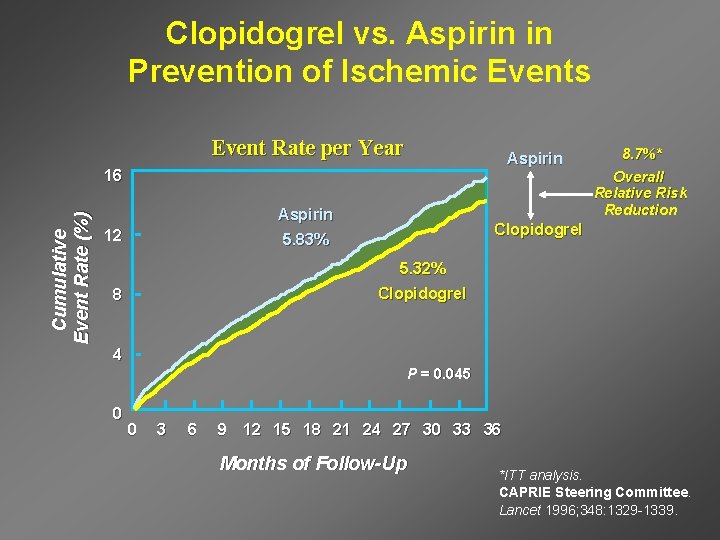

Clopidogrel vs. Aspirin in Prevention of Ischemic Events Event Rate per Year Aspirin Cumulative Event Rate (%) 16 Overall Relative Risk Reduction Aspirin 12 8. 7%* Clopidogrel 5. 83% 5. 32% 8 Clopidogrel 4 P = 0. 045 0 0 3 6 9 12 15 18 21 24 27 30 33 36 Months of Follow-Up *ITT analysis. CAPRIE Steering Committee. Lancet 1996; 348: 1329 -1339.